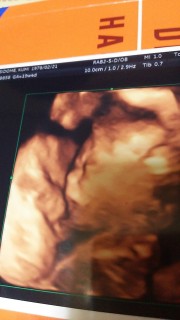

ヤバイ❗この写真見たら子供が大好きになりました。可愛すぎ。体重300gです。性別見ましょうか?言ゎれて期待したところお股閉じててお見送りになりました。笑